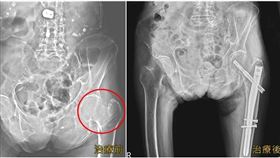

骨頭蛀掉崩塌!鼠蹊部痛竟髖關節壞死

遊覽車司機周先生從去年開始出現鼠蹊部、臀部痠痛。一開...